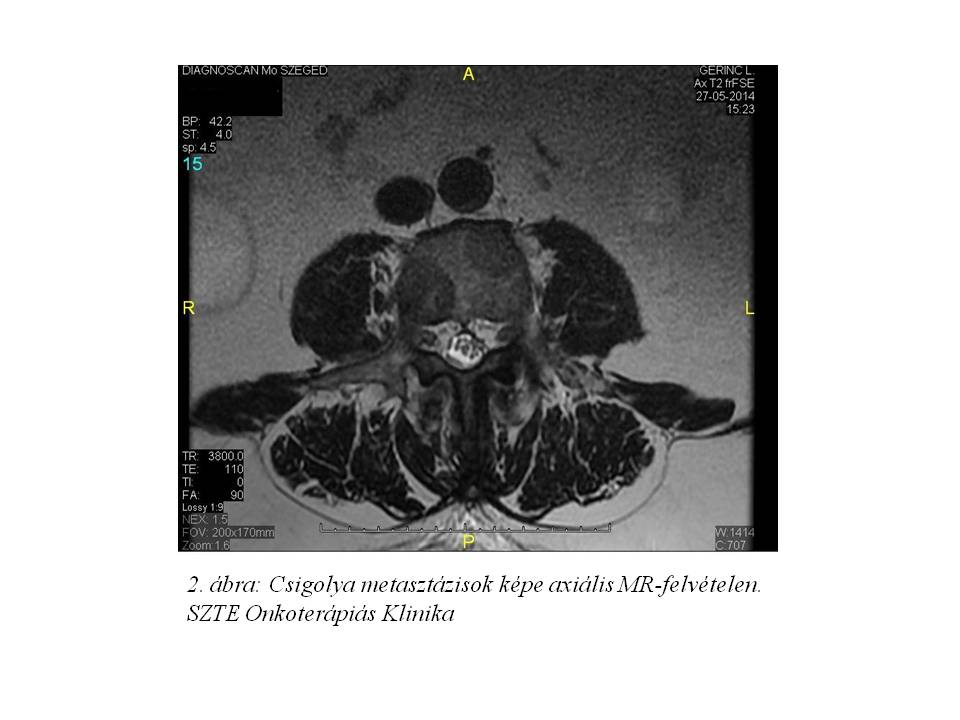

2014 májusában intenzív, mozgásra fokozódó derékfájdalmai jelentkeztek. Sürgősségi Betegellátó Osztályon készített hasi-kismedencei CT és lumbális MR (1. ábra, 2. ábra)

Ekkor a lumbális gerinc és a medence fájdalmas területének palliatív konformális sugárkezelése történt 10 x 3 Gy dózissal, valamint zoledronsav kezelés indult. A primer tumor kutatás első lépéseként a 13 évvel korábban történt radikális prosztata eltávolítás ellenére PSA meghatározást végeztünk a csontáttétek típusos lokalizációjára, valamint a beavatkozás gyors és egyszerű elvégezhetőségére való tekintettel. A PSA szintje a referencia értéket többszörösen meghaladta (126.8 ng/ml), mely alapján elsődleges daganatként prosztata karcinómát valószínűsítettünk.